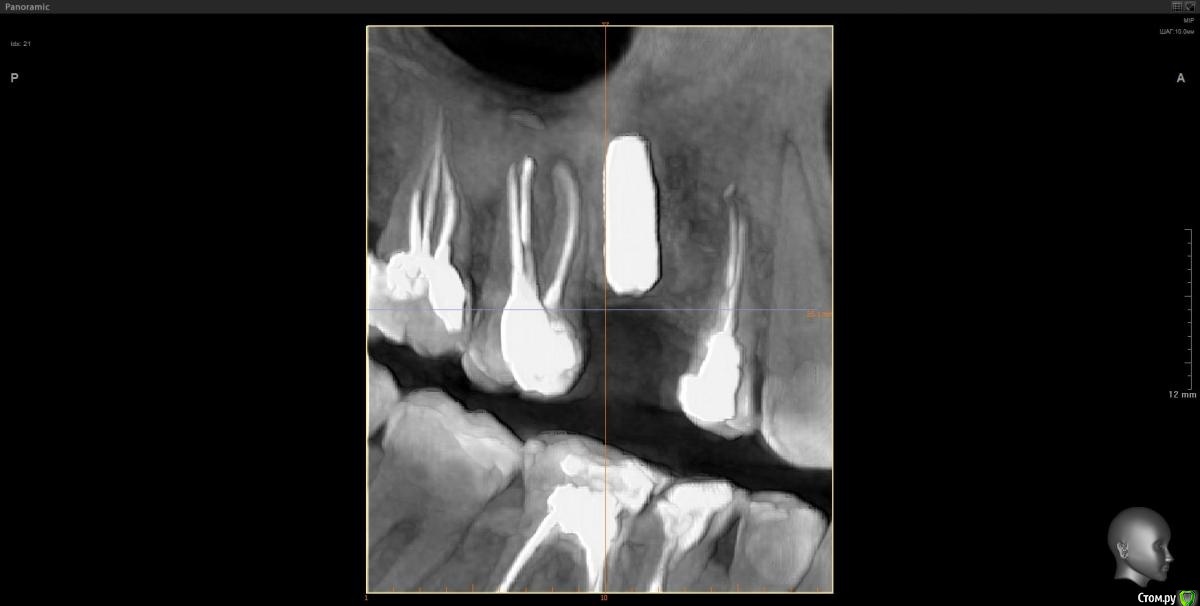

Tatiana72 Опубликовано 27 октября, 2020 Автор Поделиться Опубликовано 27 октября, 2020 Добрый вечер!Выкладываю скрины срезов Ссылка на исследованиеhttps://yadi.sk/d/ViQR0U6R2QjHzg Ссылка на комментарий

Дмитрий М Опубликовано 28 октября, 2020 Поделиться Опубликовано 28 октября, 2020 Добрый вечер!Выкладываю скрины срезовImage4.jpgImage5.jpgImage9.jpg Ссылка на исследованиеhttps://yadi.sk/d/ViQR0U6R2QjHzg не волнуйтесь всё хорошо, по КТ корень зуба не задетесть небольшой очаг разряжения на одном из апексов, обратитесь к стоматологу 1 Ссылка на комментарий